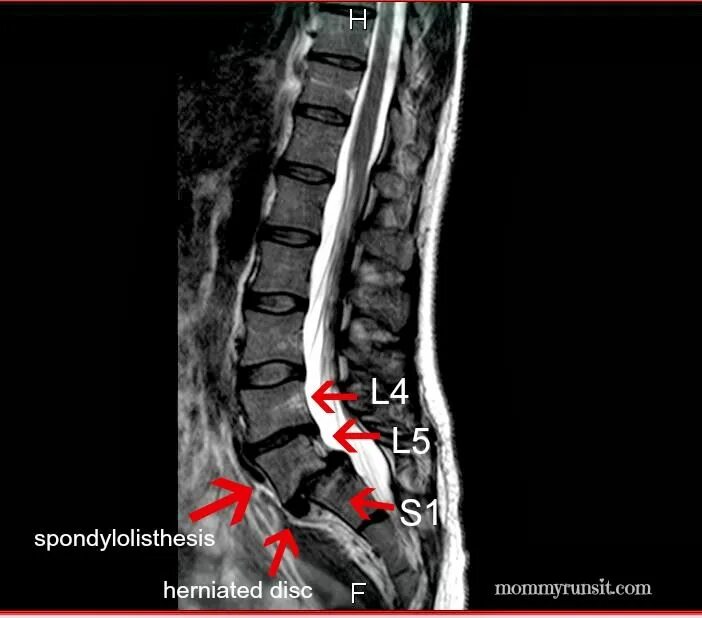

L5 s1 форум